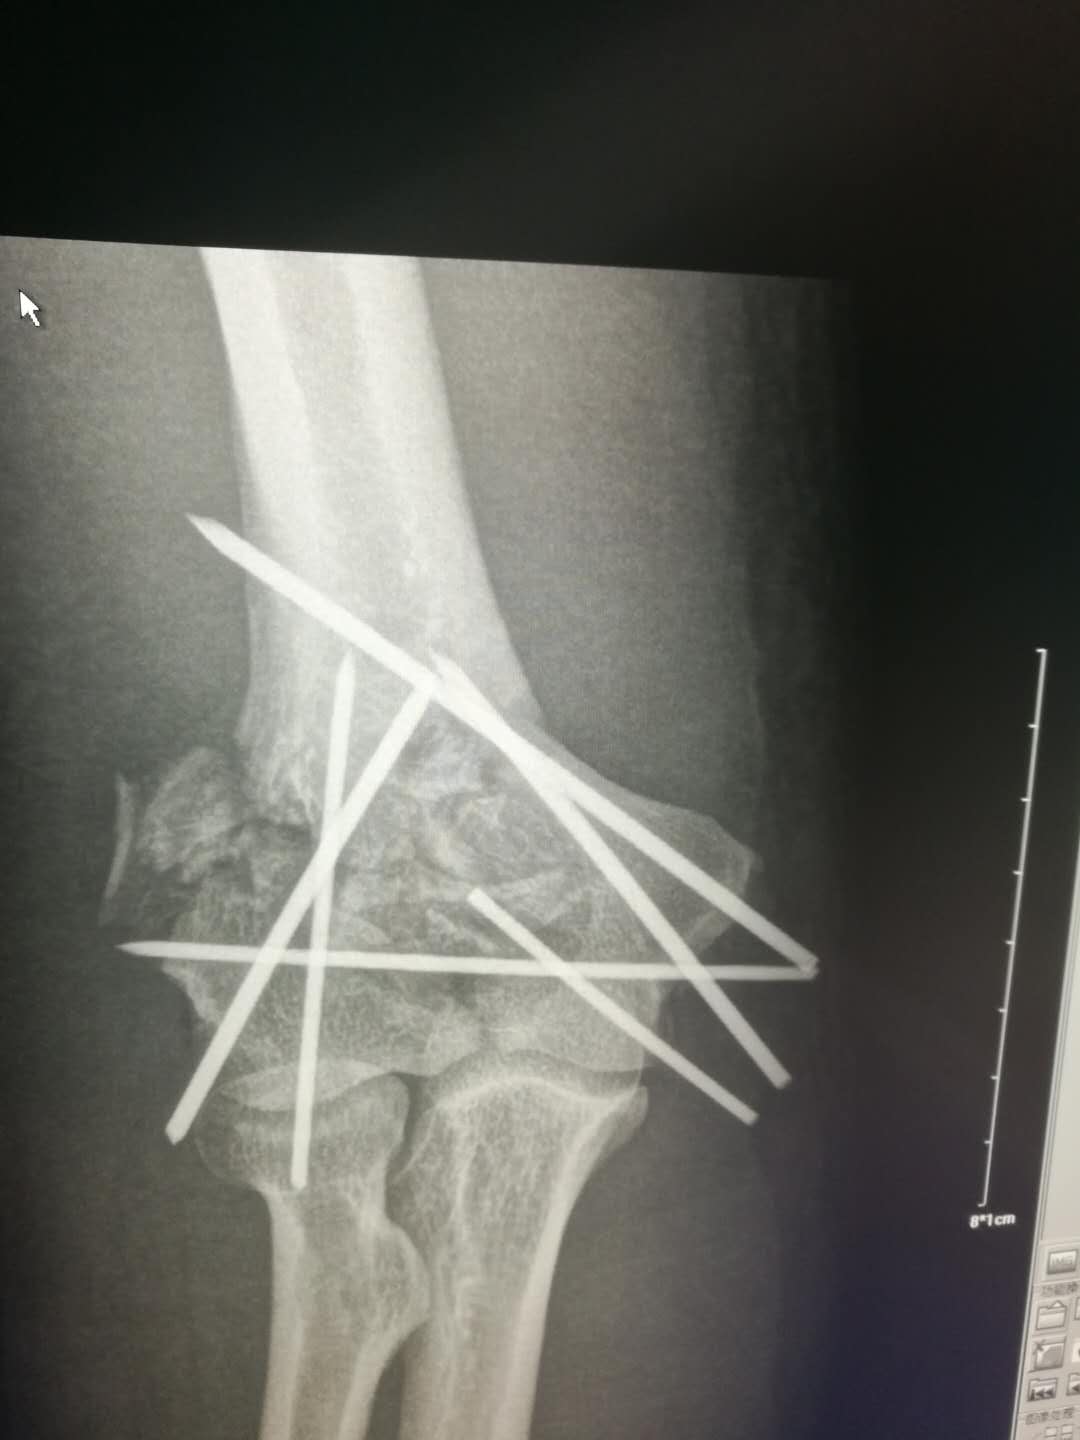

李某因不慎自约4米高处坠落,右肘部着地摔伤入院。 骨一科高长明副主任医师接诊病人后,为病人进行了仔细的查体,见其右肘部肿胀畸形,肘后有一伤口,骨头自伤口戳出,鲜血不断流淌,按压可触及明显的骨擦感,拍片见右肱骨髁粉碎性骨折,诊断为右肱骨髁开放性粉碎性骨折。开放性骨折需及早手术,但骨折粉碎,手术难度大,高医师当机立断,即刻实施手术。

术中见患者的肱骨髁已碎成20余块大小不等的骨块,均分离移位,高医师凭借丰富的手术经验,耐心地将碎骨块一块一块的拼接固定,历时3个小时,终于将骨块完好拼接,恢复了其原本的样貌。